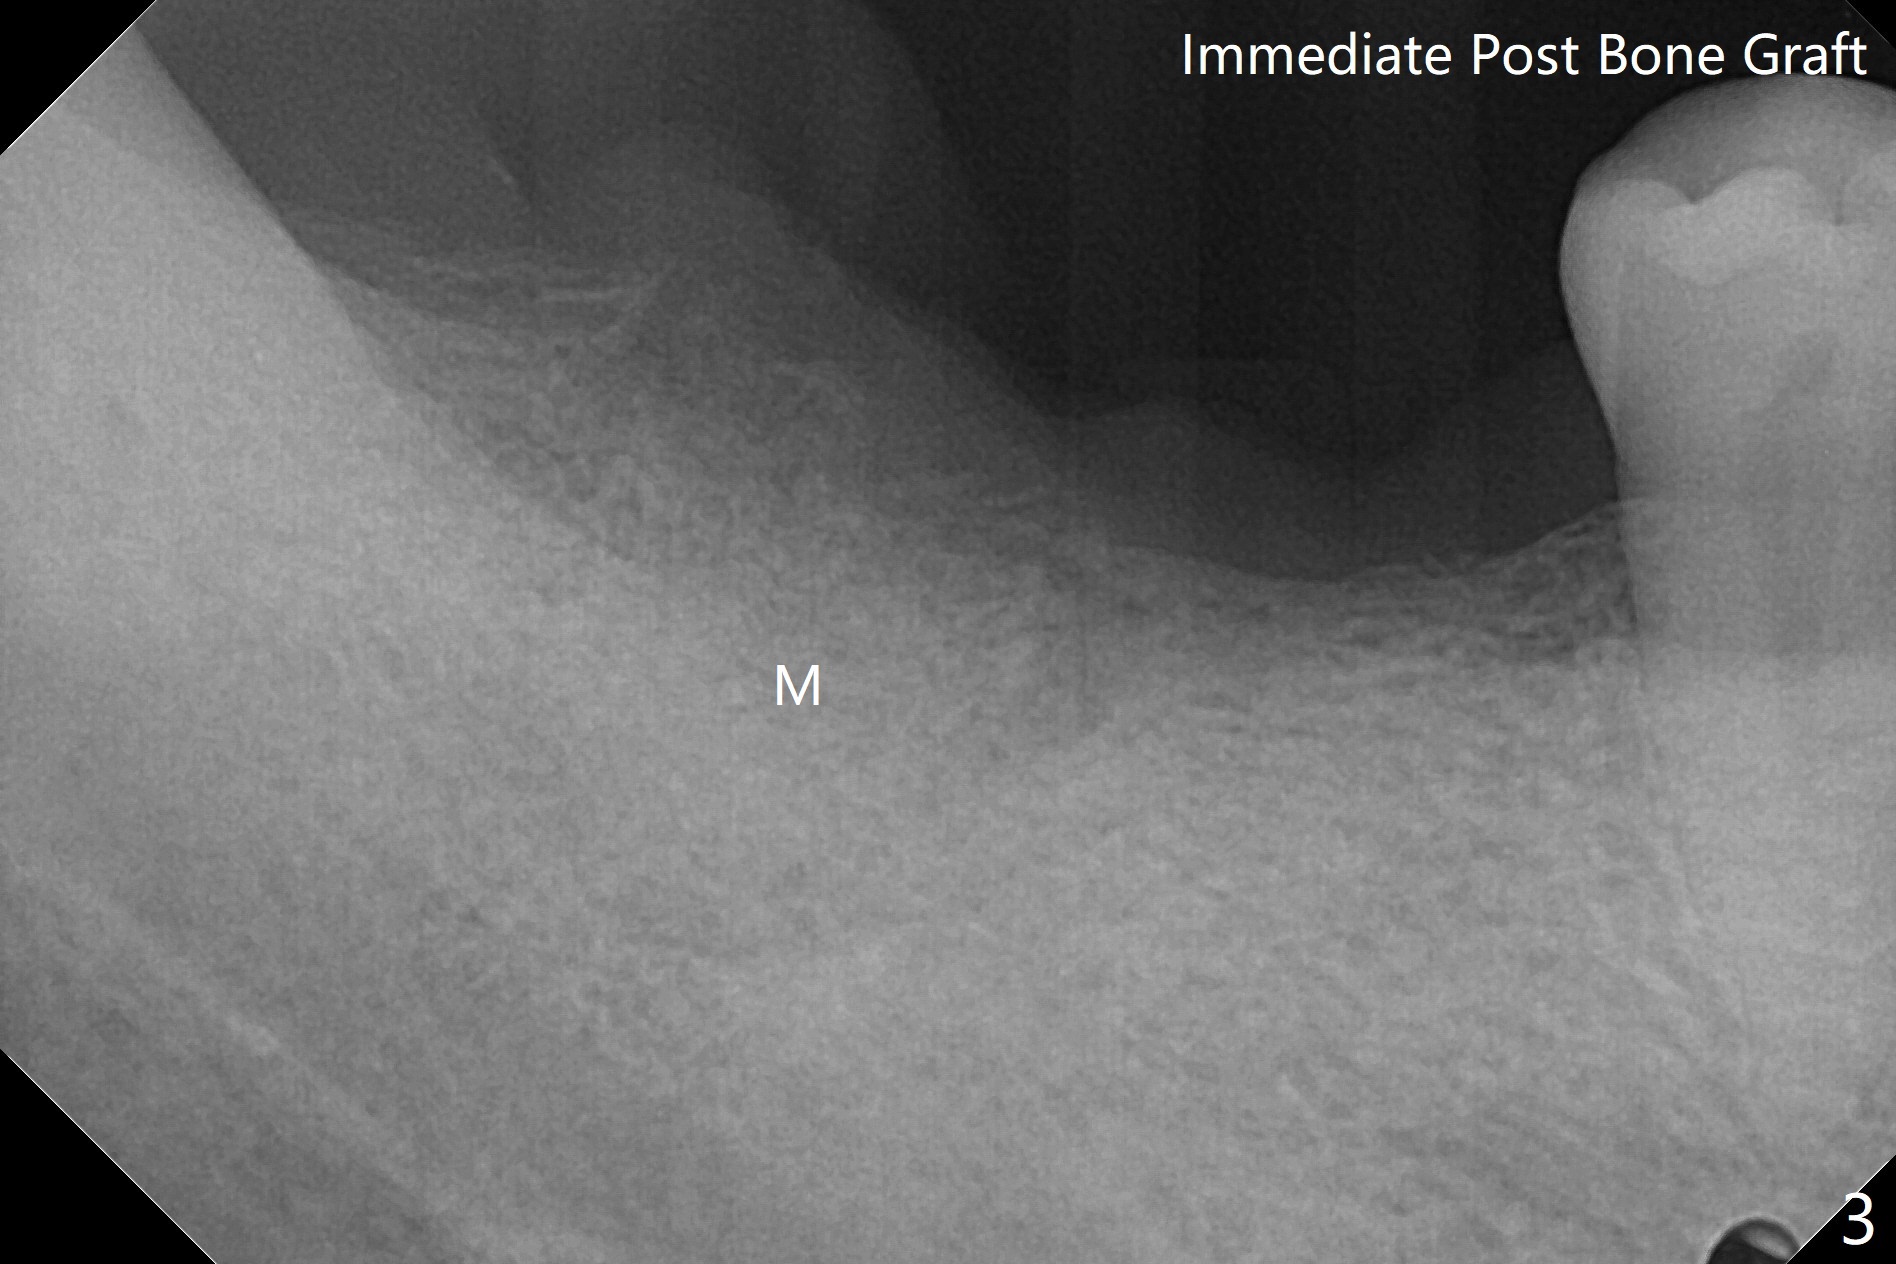

Since the tooth #31 is mesially shifted and tilted with mobility, it would not be a good distal anchor tooth for #30 implant placement with a surgical guide. It is extracted when an implant is placed at #3 so that autogenous bone harvested from the osteotomy at #3 will be mixed with allograft (Vanilla) and alloplast (Osteogen) for #31 socket preservation (Fig.3 M). After Osteogen plug and 6-month membrane are placed over the mixed graft, the socket is approximated with 5-0 PGA (Fig.1,2). The 6-month membrane appears to be retained 5 days postop (Fig.4). The socket reduces substantially nearly 1 month postop (Fig.5,6). The small 2nd molar socket (as compared to the 1st molar one) heals quick. PGA suture should be used more often (for more cases and repeat multiple times for secure closure). The bone density in the graft area increases 4 months postop (Fig.7). The graft remains in site nearly 11 months postop (Fig.8). The ridge #30 will be split with guide. In fact there is not much problem when the osteotomy moves lingual.